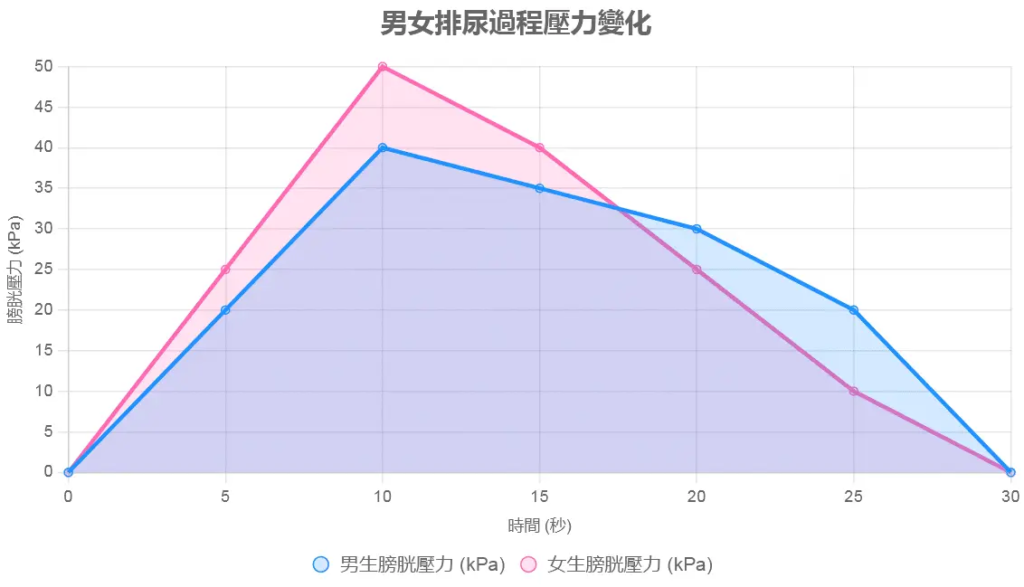

排尿過程時間線

描述:

此線圖展示排尿過程的時間線(從膀胱充盈到尿液排出),比較男女在各階段的時間差異。橫軸為時間(秒),縱軸為膀胱壓力(kPa)。圖表包含兩條曲線:

- 男生曲線(藍色):顯示膀胱壓力從0秒(尿意產生,約300-500ml)上升至5秒(逼尿肌收縮),10秒時尿流開始,30秒結束(尿流速15-20ml/s)。曲線平緩,反映較長尿道導致的較慢流速。

- 女生曲線(粉紅色):顯示相似壓力上升,但尿流於8秒開始,25秒結束(尿流速20-30ml/s)。曲線較陡,反映短尿道導致快速排出。

原因分析:

線圖顯示,女生尿流開始與結束時間較短(約17秒 vs 男生20秒),因尿道短,尿液流速快,需更強外括約肌力中斷。男生壓力變化較平緩,反映尿道阻力與括約肌控制力較佳。